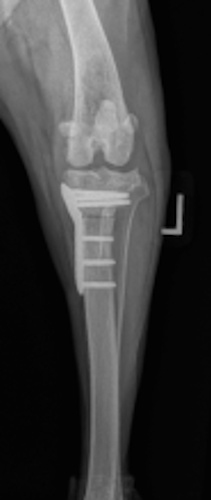

Tibial Plateau Leveling Osteotomy (TPLO) - additional information

An osteotomy is a surgical cut in a bone. In the cruciate deficient stifle, a cut is made in the top of the tibia. The top portion of bone that contains the articular surface is rotated to level it. The two pieces of bone are held in place with a metal plate and screws.

Post Surgical Radiographs

While the patient is still anesthetized, the patient is taken into radiology for post-surgery radiographs (X-rays). The radiographs are assessed to measure the new tibial plateau angle. We are aiming for 5-6 degrees relative to the long axis of the tibia. The apparatus (plate and screws) are assessed for size and appropriate position.